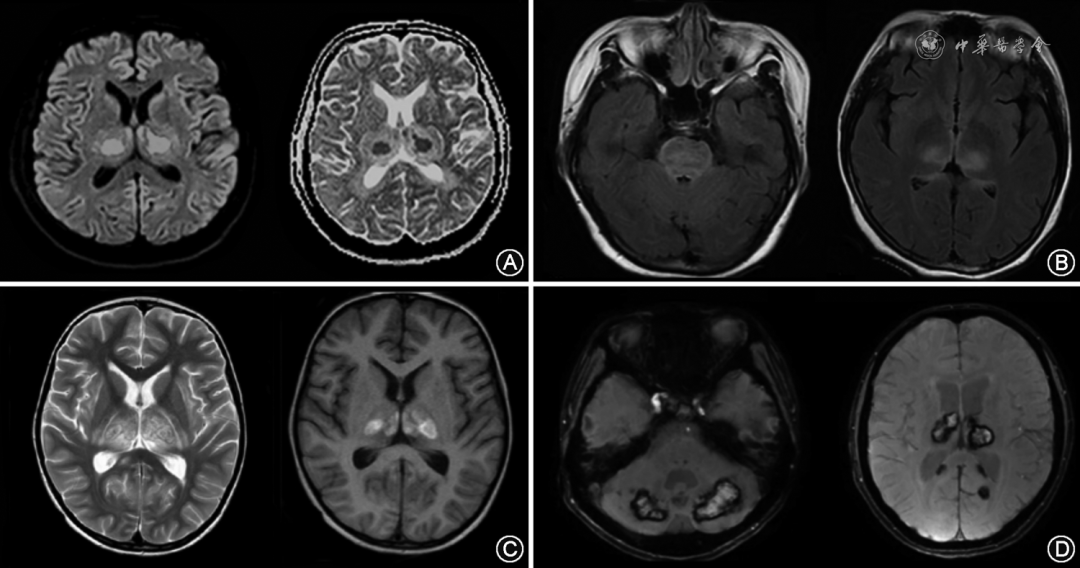

本组18例患者中共有17例接受了头颅MRI检查,其中9例报告了头颅MRI检查的时间,具体为起病2~21[4(2,21)]d。头颅MRI均可见双侧丘脑对称性高T2、高FLAIR信号并伴明显肿胀。病灶在T1序列多表现为等/低信号,部分混杂高信号;在弥散加权成像序列多表现为细胞毒性水肿(DWI高信号、表观弥散系数低信号),部分病灶周围可伴血管源性水肿(DWI低信号、表观弥散系数高信号)。同时,部分病灶在磁敏感加权成像序列为低信号,提示存在含铁血黄素沉积。部分患者经免疫治疗后症状好转,复查头颅MRI病灶亦较前吸收、缩小。1例患者未行头颅MRI检查,其头颅CT检查可见双侧丘脑对称低密度病灶。在病灶部位分布方面,除丘脑部位全部患者均受累(18/18)之外,ANE患者以皮质(8/18)、脑干(7/18)、皮质下白质(6/18)、小脑(6/18)、基底节区(4/18)受累较为多见。ANE患者典型影像学表现结果详见图1。

图1  不同急性坏死性脑病患者的头颅磁共振成像(MRI)结果。A:弥散加权成像(DWI)示双侧丘脑病灶核心呈高DWI、低表观弥散系数(ADC)信号,外周呈低DWI、高ADC信号;B:液体衰减反转恢复(FLAIR)序列示脑桥及双侧丘脑病灶呈高FLAIR信号;C:双侧丘脑病灶呈长T2、混杂T1信号影;D:磁敏感加权成像序列示双侧小脑、丘脑、枕叶皮质下病灶存在含铁血黄素沉积

Figure 1  The magnetic resonance imaging results of different acute necrotizing encephalopathy patients